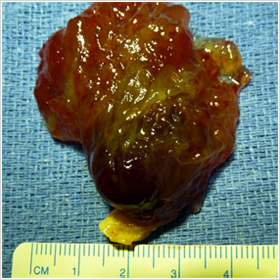

Après les myxomes, les tumeurs bénignes les plus fréquentes sont les lipomes (20 %) qui sont des masses de cellules graisseuses (adipocytes) encapsulées. Ces lipomes siègent au niveau des cavités cardiaques et du péricarde qui est l’enveloppe fibreuse qui entoure le cœur.

S’ils sont intra-cardiaques ils peuvent donner des signes d’obstruction au passage du flux sanguin. S’ils sont extra-cardiaques ils peuvent donner des signes de compression du coeur.

Le traitement est chirurgical lorsqu’ils donnent des signes cliniques. L’intervention est plus ou moins complexe selon la taille et la localisation du lipome.

Très volumineux lipome du ventricule droit